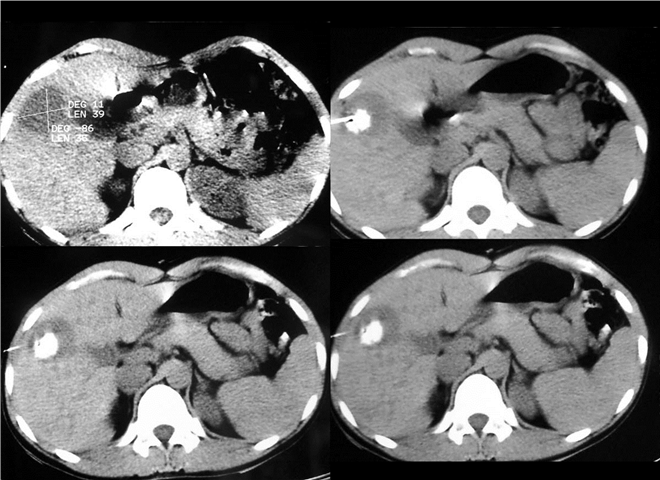

13_CT增强扫描